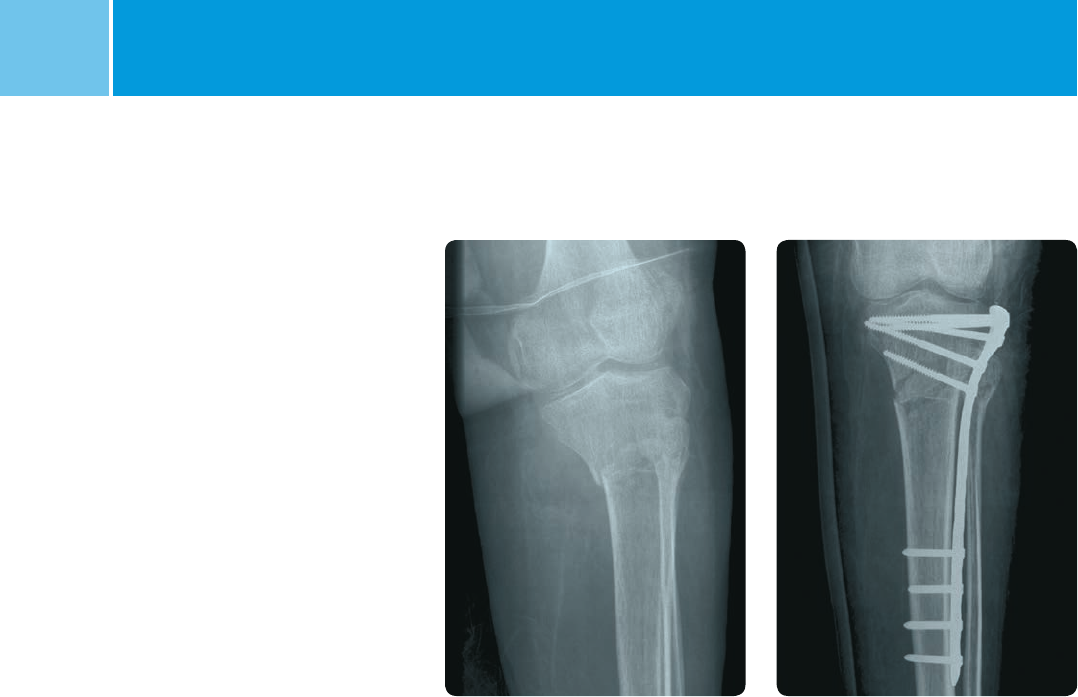

Case 2: 41-A2 fracture

(OTA classification,

MIS surgical procedure)

PostoperativePreoperative